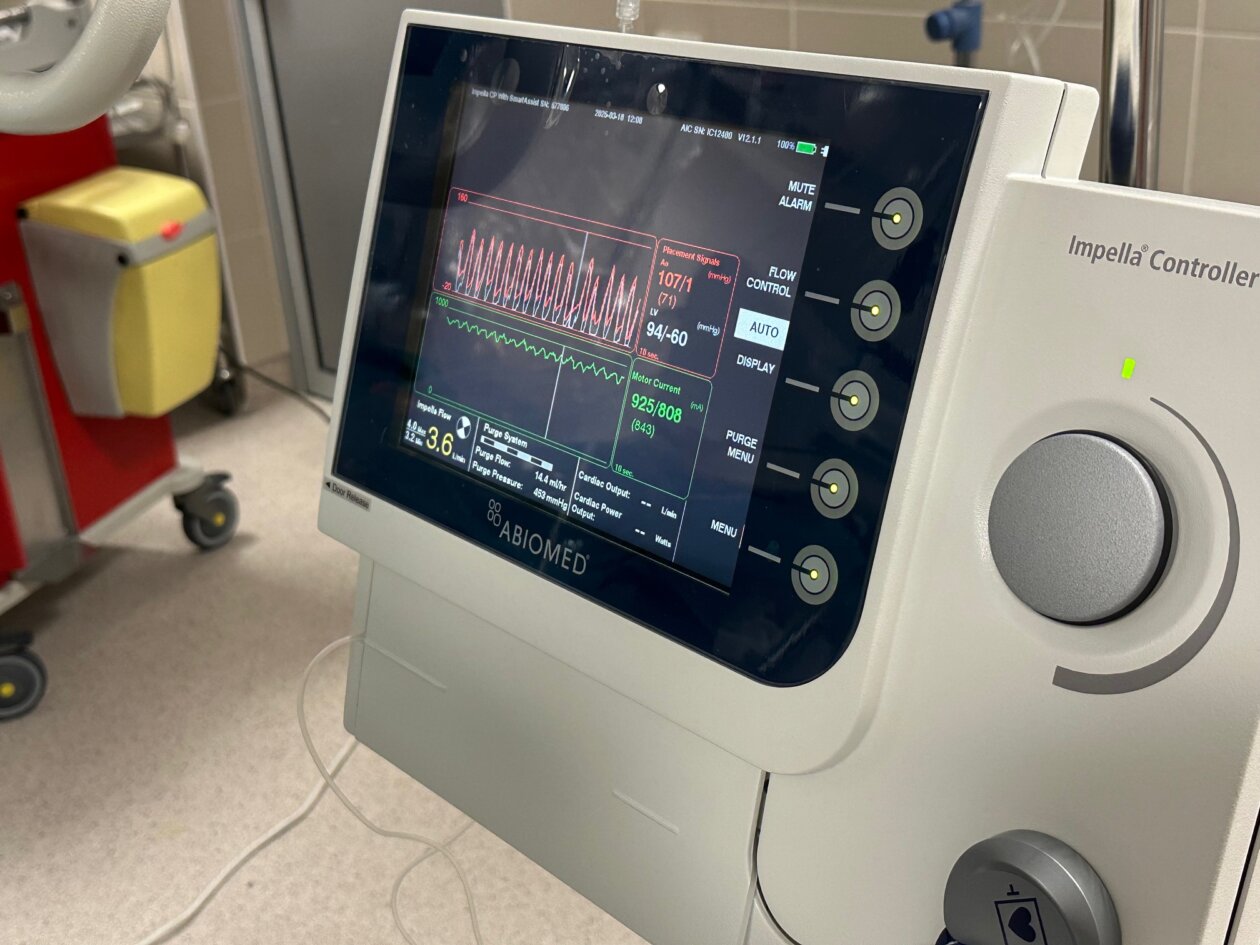

“Impella CP koristi tehnologiju perkutane srčane pumpe koja se kroz femoralnu arteriju uvodi u lijevu srčanu klijetku i pruža potporu radu srca kod visokorizičnih zahvata i srčanog zatajenja. Uređaj osigurava protok krvi do 4.3 litre u minuti, čime značajno smanjuje opterećenje srca i pomaže pri održavanju cirkulacije.

Ova tehnologija predstavlja vrhunac suvremene medicinske skrbi za pacijente u kardiogenom šoku ili pri izvođenju visokorizičnih PCI zahvata.

Impella sustav postaje standard u svjetskoj i hrvatskoj praksi te je uvršten u Nacionalni kardiološki tender i time postaje sve važniji alat u borbi za život pacijenata s teškim srčanim stanjima”, izjavio je voditelj Odjela intervencijske kardiologije Mihajlo Kovačić, dr.med. spec.interne medicine, subspec. kardiologije.